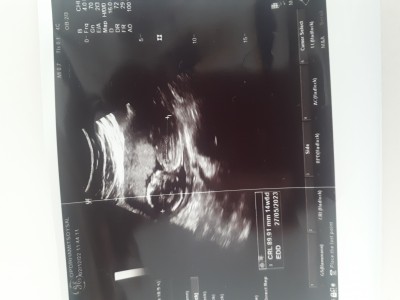

Sizce kızmı erkekmi özele gidiyorum doktorum daha erken cinsiyeti soylemem icin dedi

Gebelik haftası 14+3